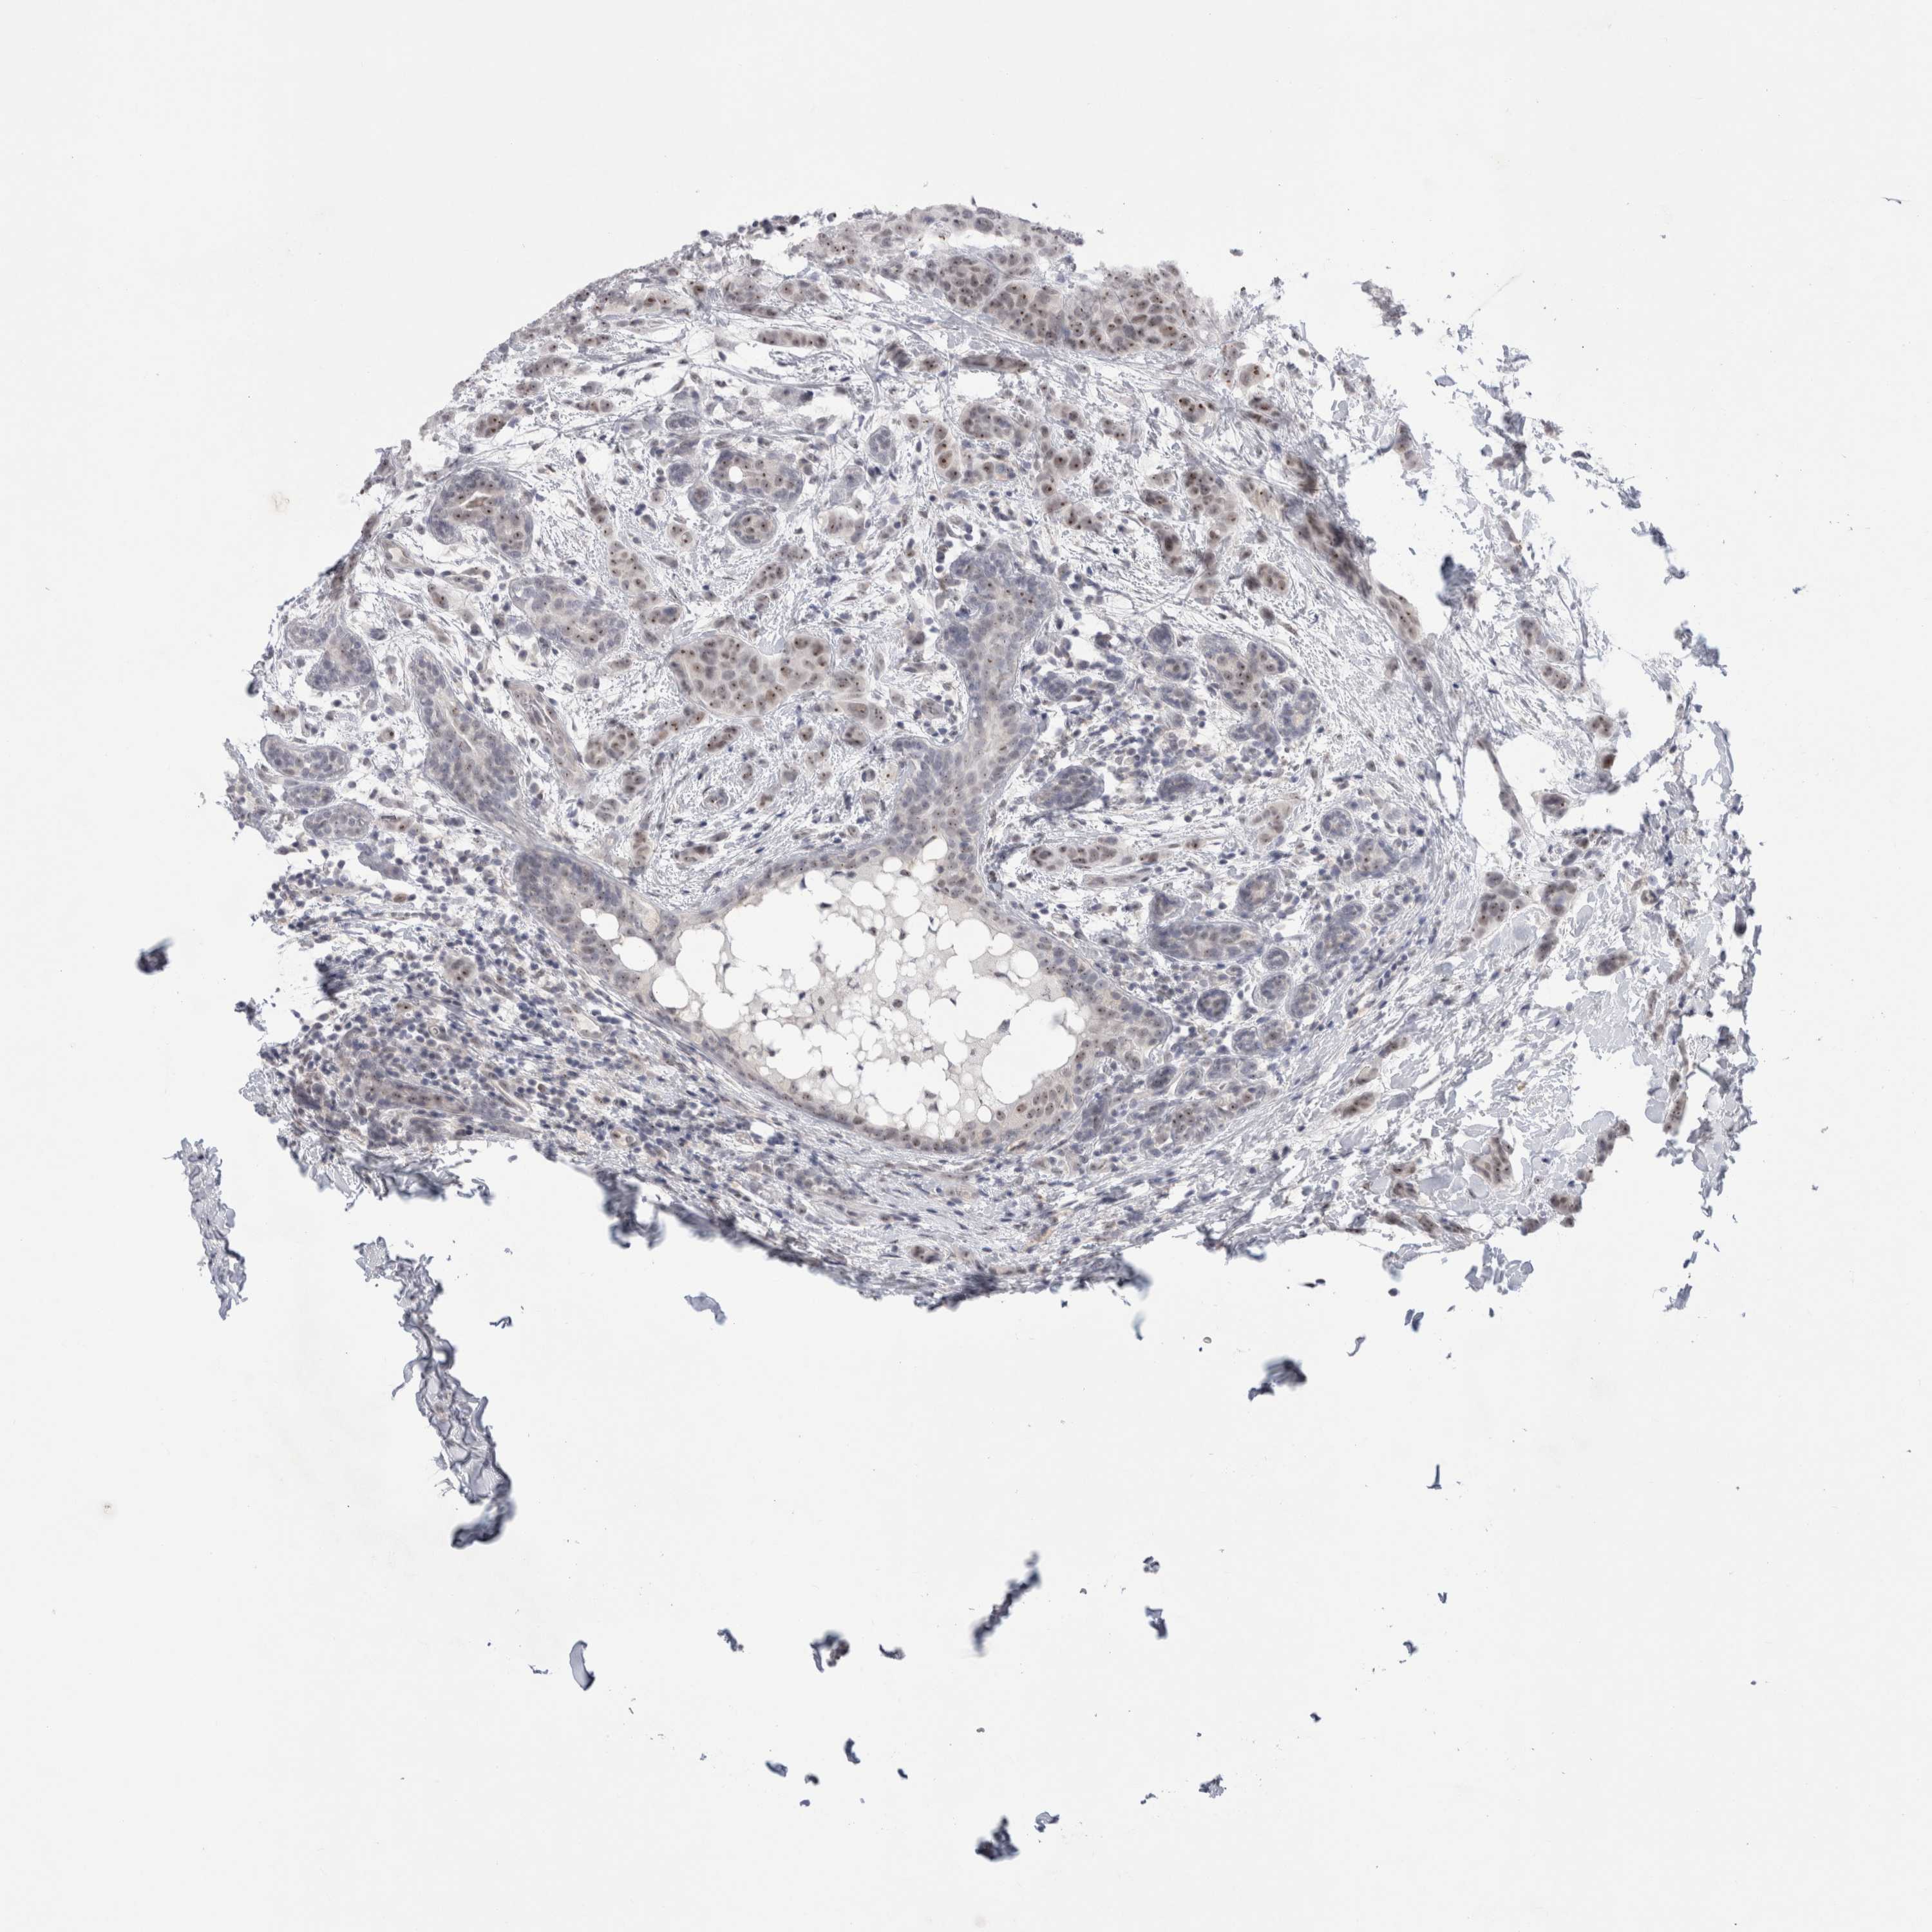

CANCER BREAST CANCER Show tissue menu

BRCA TCGA BRCA VALIDATION PROTEIN EXPRESSION

ANTIBODIES

AND

VALIDATION